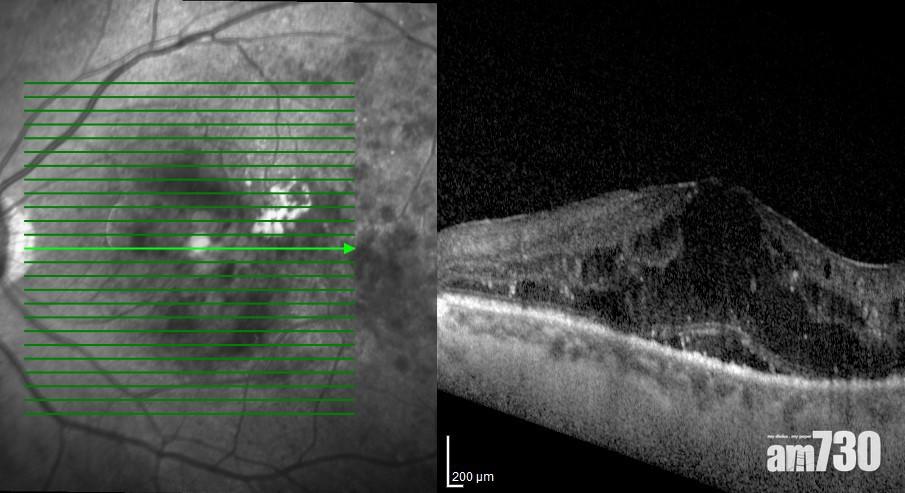

在糖尿上眼的併發症中,糖尿黃斑水腫是視力變差的最常見原因。醫生可通過眼底檢查、光學相干斷層掃描和眼底螢光血管造影作檢查。治療可分為激光治療及眼內注射,激光治療是直接將激光打在滲漏的區域上,阻止繼續滲漏並加速身體吸收已滲出的水分,新一代微脈衝激光能有效改善水腫及視力,同時避免視網膜神經組織的損傷;眼內注射的藥物包括「抗血管內皮細胞生長因子」及類固醇藥物,能有效減退黃斑水腫和改善視力。醫生會因應患者的情況,選擇適當的治療方案。

光學相干斷層掃描能幫助診斷糖尿黃斑水腫。